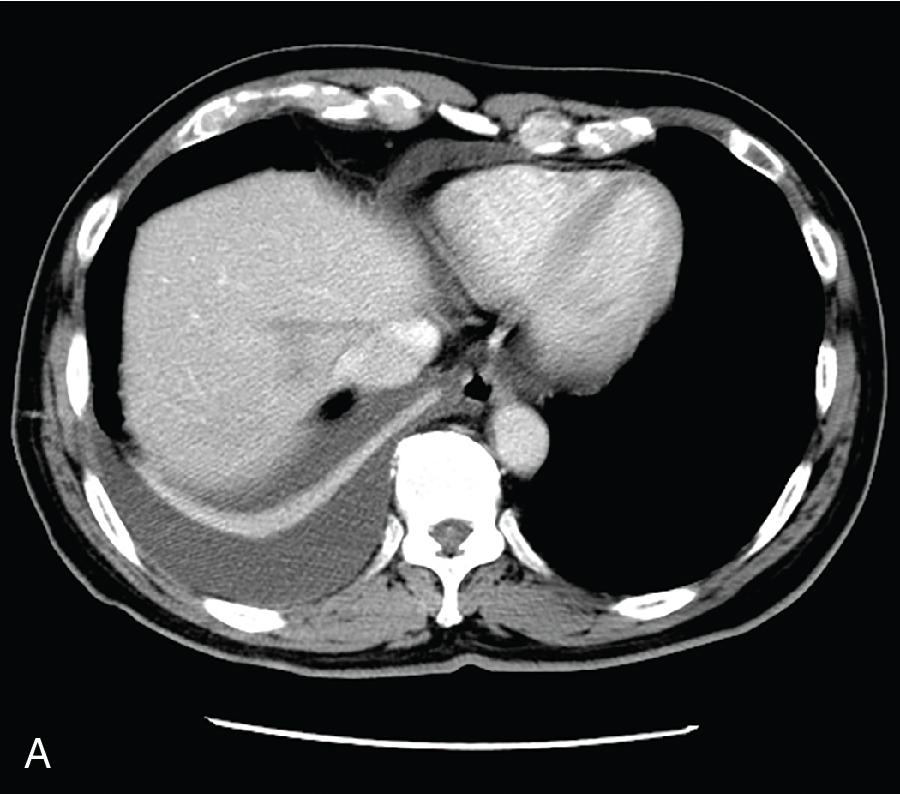

Twenty percent of patients present with isolated extrahepatic CBD dilatation, gallbladder stones, and a diseased gallbladder. In acute cholangitis, where the CBD is obstructed by stone, the gallbladder may be distended. Edema, empyema, gangrenous change, and perforation of the gallbladder can complicate biliary obstruction. With recurrent episodes of cholangitis and gallbladder stones, initial drainage by ERCP, surgical drainage procedures, and cholecystectomy may be required for effective management of extrahepatic manifestations of RPC ( Fig. 44.5 ).

FIGURE 44.5, A and B, Contrast computed tomography (CT) scan of a patient with extrahepatic recurrent pyogenic cholangitis, which showed dilated common bile duct (CBD) and distended gallbladder. There was a large stone at the lower end of the CBD. This patient had undergone a robotic-assisted cholecystectomy and choledochojejunostomy. The follow-up CT scan showed no more stone and no dilatation of bile ducts (see Chapter 16 ). C, Endoscopic retrograde cholangiopancreatography showing dilated CBD and left intrahepatic duct with no stricture in the intrahepatic ductal system (see Chapter 30 ).